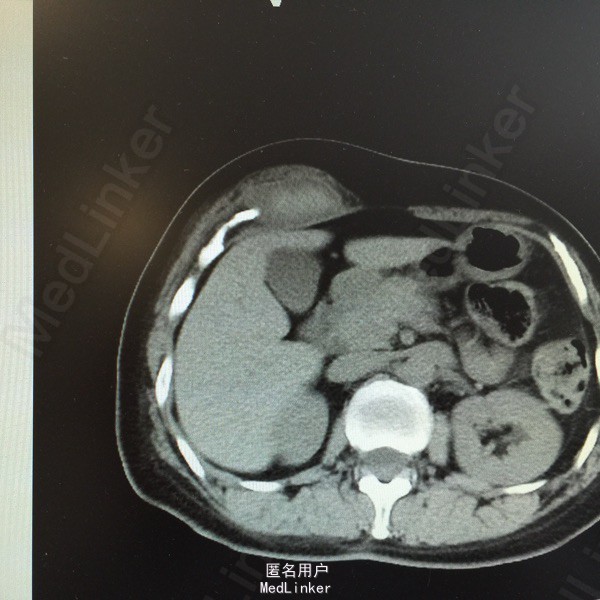

主诉:腹痛、发现腹部肿物15天。 现病史:患者于15天前因运动后突发腹痛,为持续性胀痛,伴停止排气,无恶心、呕吐,后觉疼痛缓解,并发现腹部肿物,压痛明显。当时于外院行超声:右上腹患者所指处肌层见无回声,约8*6cm大小,形态规则,边界清。现患者无诉疼痛,自觉肿块变小,为进一步诊治,收入我科。 既往史、家族史均无特殊。 查体:全腹软,右上腹近季肋部可触及一5*2cm包块,质软,活动差,压痛明显,周围皮肤无红肿、无溃烂。余无特殊。 辅助检查: 超声:患者右上腹腹壁层内肌层后方见无回声,大小约5.4*2.3cm,形态规则,边界尚清,内见少许分隔。考虑右上腹腹壁内囊性包块。 CT:右上腹季肋部腹直肌鞘内梭形软组织密度影,病变中央密度高,约65HU,边缘密度稍低,约33HU。印象:右上腹腹直肌鞘内梭形高密度影,血肿不除外。 大家考虑?